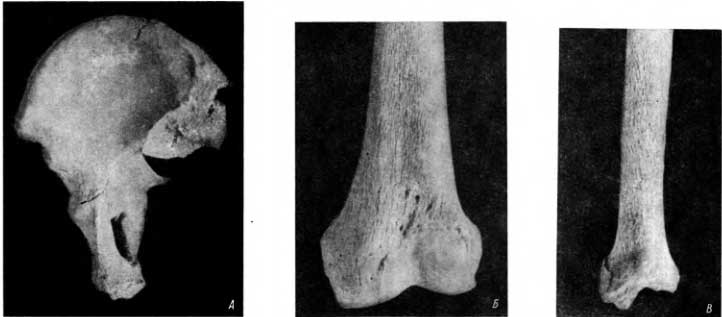

Рис. 56. А — проявления болезни Пэджета в безыменной кости, перестройка и разволокнение кортикального слоя; Б — проявления болезни Пэджета бедренной кости того же человека, аналогичные изменения, но на большем протяжении; В — проявления болезни Пэджета в большеберцовой кости.

В обеих безыменных костях указанного скелета были обнаружены проявления болезни Пэджета. Они сводились к своеобразной перестройке структуры поверхностного слоя компактного вещества кости, к разволок-нению пограничной линии у входа в малый таз и на небольшом протяжении в смежных участках (рис. 56, А).

В средней и нижней трети бедренных костей на их передней поверхности хорошо прослеживалась аналогичная перестройка кости. Разволокненные пластинки поверхностного слоя кортикального вещества располагались параллельно друг другу по длиннику кости. На всем этом протяжении разволокненная структура была выражена в одинаковой мере (рис. 56, Б).

Передняя поверхность обеих большеберцовых костей в средней и нижней третях характеризовалась аналогичной, но несколько более выраженной перестройкой структуры кортикального слоя (рис. 56, В). На контактных снимках в обычно применяемых проекциях (т. е. в задней и боковой) эти изменения не определялись. Не было обнаружено остеопороза и других симптомов, рассматриваемых в качестве ранних симптомов болезни Пэджета. На контактном снимке в передней проекции это разволокнение улавливалось лучше, чем на снимке бедренной кости, и все же не адекватно тому, что дает осмотр кости.